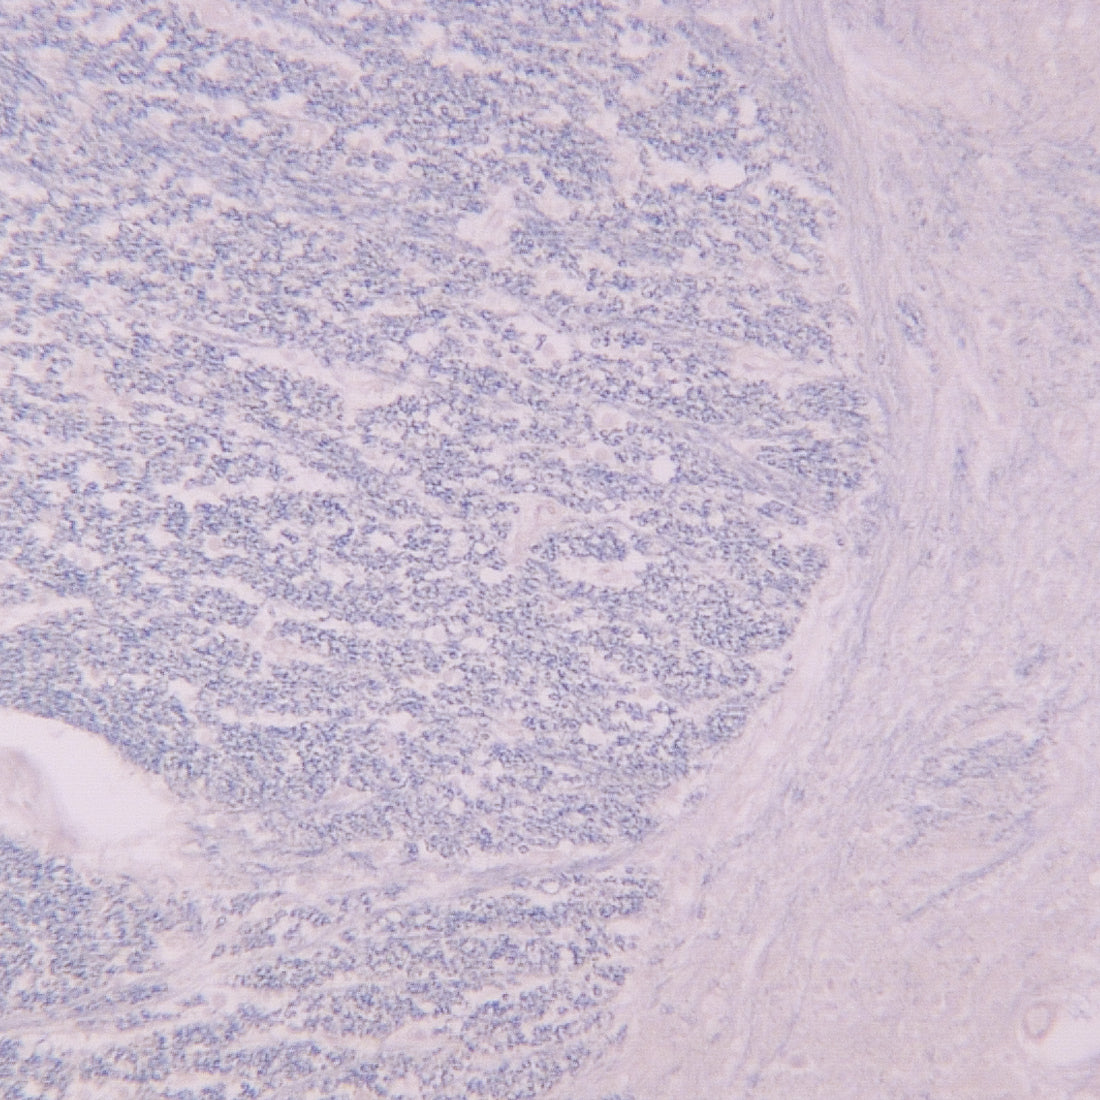

Fast Blue是一种荧光染料,常用作神经元示踪剂,并被称为亲水性逆行示踪剂。FB可以单独使用,也可以与其他类型的荧光逆行和顺行示踪染料结合使用。其他神经元示踪剂如真蓝(True Blue)、伊文思蓝 (Evans Blue)和核黄(Nuclear Yellow)也常与FB联合使用。

Granular Blue, GB是一种荧光逆行示踪剂,用于周围神经系统的实验研究,以确定投射到特定区域的神经元的数量和起源。逆行示踪技术能够详细评估从单一神经元群体到整个神经系统中各种靶点的神经元连接。这些技术允许“绘制”特定结构(例如眼睛)中的神经元与大脑中靶神经元之间的连接图。

True Blue (TB)是一种荧光逆行示踪剂,用于周围神经系统实验研究,以确定投射到特定区域的神经元的数量和起源。逆行示踪技术能够详细评估从单一神经元群体到整个神经系统中各种靶点的神经元连接。这些技术允许“绘制”特定结构(例如眼睛)中的神经元与大脑中靶神经元之间的连接图。

在大鼠中,TB 能有效地进行长距离转运,从脊髓到大脑皮层,产生神经元细胞体胞浆、核仁、近端树突和轴突的蓝色荧光标记 。当与二氨基黄 (Diamidino Yellow, DY) 结合使用时,TB 在旨在证明发散性轴突侧支存在的双重标记实验中效果良好。